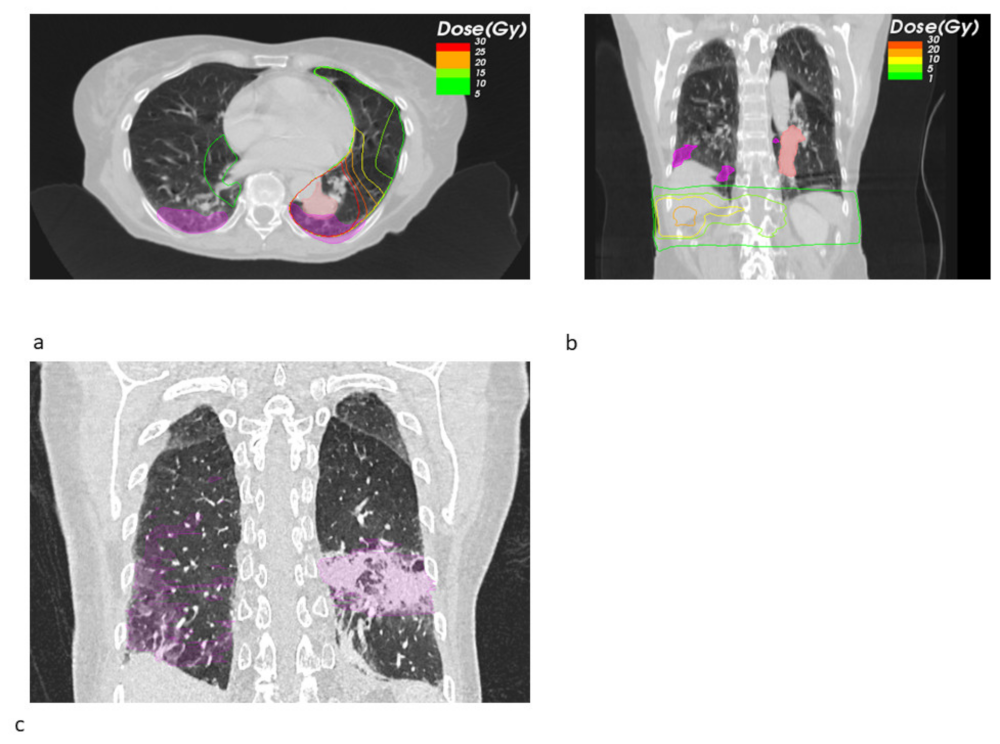

Looking at the dosimetric results in more detail, we observed a trend towards a decreased fraction of the pneumonitis volume receiving a high dose of EQD2 > 20 Gy SBRT + ICB (22.26% vs. 71.14%, p = 0.549), whereas the mean low dose fraction with EQD2 < 10 Gy was numerically larger (39.02% vs. 26.99%). Figure 1 shows the pneumonitis extensions and EQD isodoses for two exemplary cases from both groups. For the depicted SBRT + ICB case, the pneumonitis affects both lungs with a rather small single-sided GTV distant from the resulting radiological changes. For another patient, who received SBRT with 45 Gy in 3 fractions to a small left-sided tumor, we also found bilateral extent of pneumonitis, as shown in Figure 2. This patient received additional SBRT for liver metastasis at the same time with the same dose fractionation regime; however, the extent of pneumonitis does not correlate with the dose distribution. For dosimetric analysis, we used sum doses to prevent overestimation of the effect attributed to the lung SBRT. A third patient also showed the bilateral extent of pneumonitis. This patient received hypofractionated, contralateral mediastinal RT with 45 Gy in 15 fractions a month prior to SBRT. Since the extent of the pneumonitis volume in the contralateral right lung is more likely caused by the irradiation of the right side, we considered only the pneumonitis contour from the left SBRT side for analysis. However, to not overestimate the dosimetric effect of SBRT alone, we used the sum EQD2, as shown in Figure 3a, for dosimetric evaluation as well.

Figure 2. Transversal radiotherapy (RT) planning CT slices showing the sum EQD2 isodoses and pneumonitis contours (magenta) and GTV contours (light red) for a SBRT+ ICB case (a). This patient received simultaneous liver metastasis SBRT. The isodoses of the original treatment plan show a negligible lung dose (b). Figure (c) shows an exemplary sagittal slice from the follow-up CT showing the bilateral pneumonitis and its contours (magenta).

Figure 3. Sagittal radiotherapy (RT) planning CT slices showing the sum EQD2 isodoses and pneumonitis contours (magenta) for a SBRT+ ICB case (a). The same patient received simultaneous contralateral hypofractionated mediastinal RT with original isodoses revealing a relevant lung dose (b). Exemplary sagittal slice from the follow-up CT showing the bilateral pneumonitis and its contours (magenta) (c).